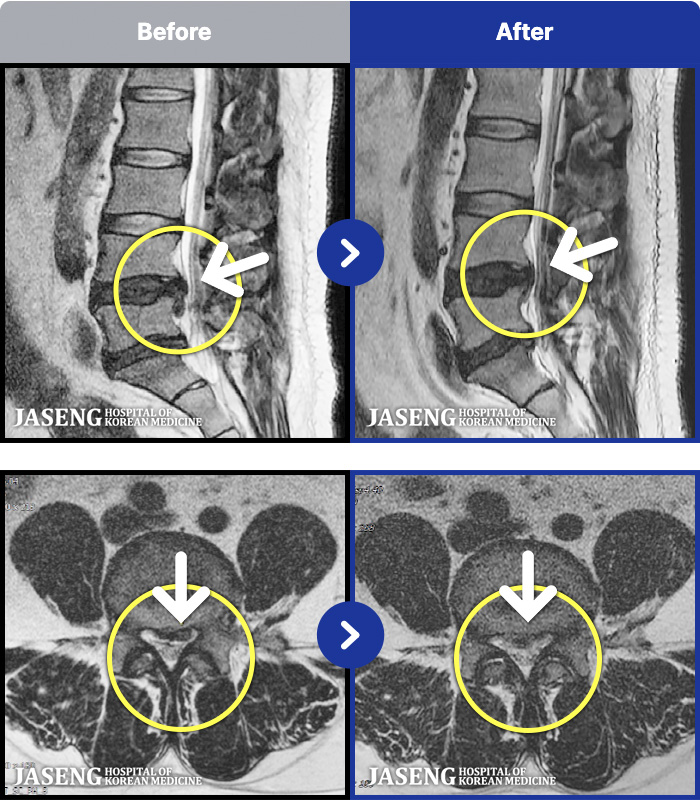

- MRI ġ

MRI ġ

1,301 MRI ũ ʸ Ȯϼ.